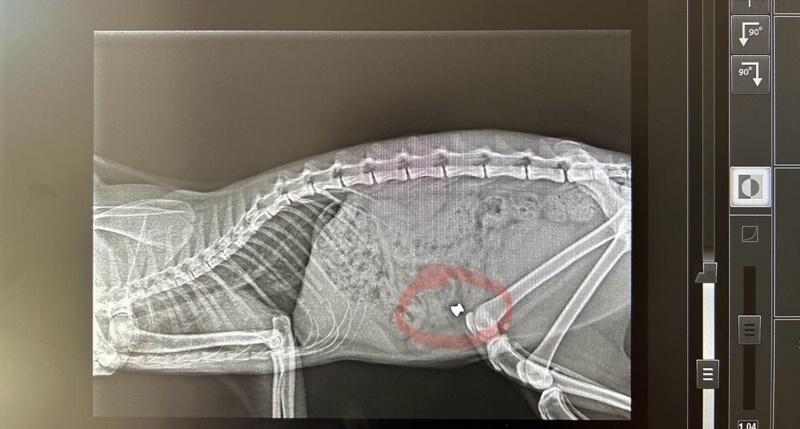

Nel quartiere popoloso di contrada Tivolille, proprio in mezzo alle abitazioni, persone non identificate stanno utilizzando fucili ad aria compressa per sparare ai gatti, utilizzando proiettili di piombo che variano da 4,5 a 6 mm, probabilmente modello diablo. La situazione è estremamente preoccupante, con alcuni gatti che sono stati uccisi e solo due sono riusciti a salvarsi grazie all’intervento tempestivo di un veterinario. Una foto della lastra mostra chiaramente il proiettile nel gatto prima che venisse operato e salvato dal medico veterinario Prof. Gianni Marinacci di Rende. Europa Verde ha deciso di offrire una ricompensa a coloro che forniranno filmati o fotografie che possano identificare gli autori di questi vili gesti. Inoltre, il partito presenterà denuncia alle autorità competenti e, nel caso venga identificato l’autore di questi delitti, chiederà un imponente risarcimento da destinare a gattili o associazioni di volontari che si occupano di piccoli felini.